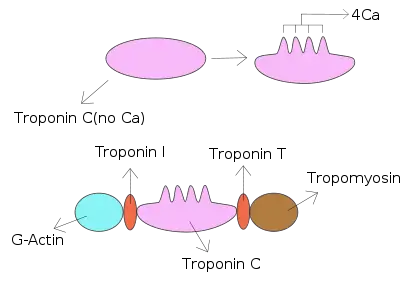

Troponin C is a protein which is part of the troponin complex. It contains four calcium-binding EF hands, although different isoforms may have fewer than four functional calcium-binding subdomains. It is a component of thin filaments, along with actin and tropomyosin. It contains an N lobe and a C lobe. The C lobe serves a structural purpose and binds to the N domain of troponin I (TnI). The C lobe can bind either Ca2+ or Mg2+. The N lobe, which binds only Ca2+, is the regulatory lobe and binds to the C domain of troponin I after calcium binding.